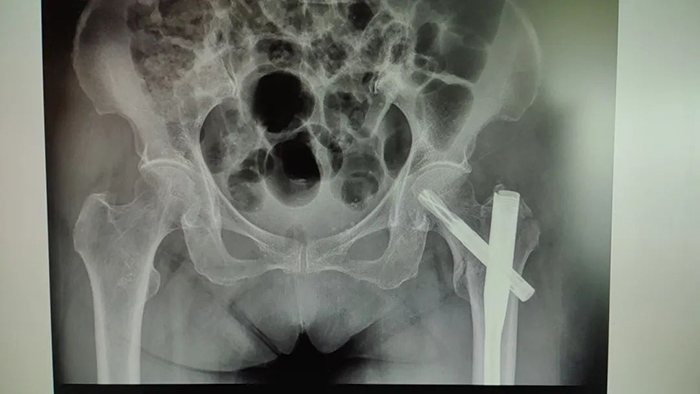

患者术前影像

虽说做手术是最有效的方式 但叶老太的手术风险很大 ◆患者血红蛋白水平较低,一旦出现手术创伤**,有可能引起消化道大出血,危及生命。 ◆患者年事已高,有高血压、冠心病、糖尿病等病史,对手术的耐受能力较差,手术并发症及手术切口不愈合、感染的风险大。 ◆患者重度骨质疏松,腰椎T值仅为-4.2,手术中轻轻一敲就有可能导致骨折劈裂。 面对复杂病情,医务科组织消化内科、血液科、手术麻醉科、心血管内科、内分泌科、中医骨伤科联合会诊,制定严谨的手术预案。 经过充分的术前准备,叶老太血红蛋白浓度补充到94g/L,陈瑞松副主任医师、冯安平主治医师为其进行左股骨粗隆间粉碎性骨折闭合复位内固定术。手术顺利完成,患者生命体征平稳。 患者术后影像 术后 中医骨伤科医护团队精心护理 叶老太恢复良好 目前已出院回家休养 ▲出院时,患者及家属向中医骨伤科医护团队送来锦旗表达感谢。 如果老人有髋部骨折方面的困扰 可至跳蛋视频